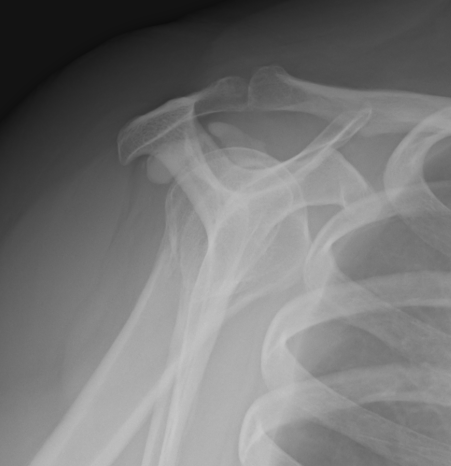

Calcific Tendonitis APSubscapularis CalciumSubscapularis Calcium Lateral

Subscapularis calcification